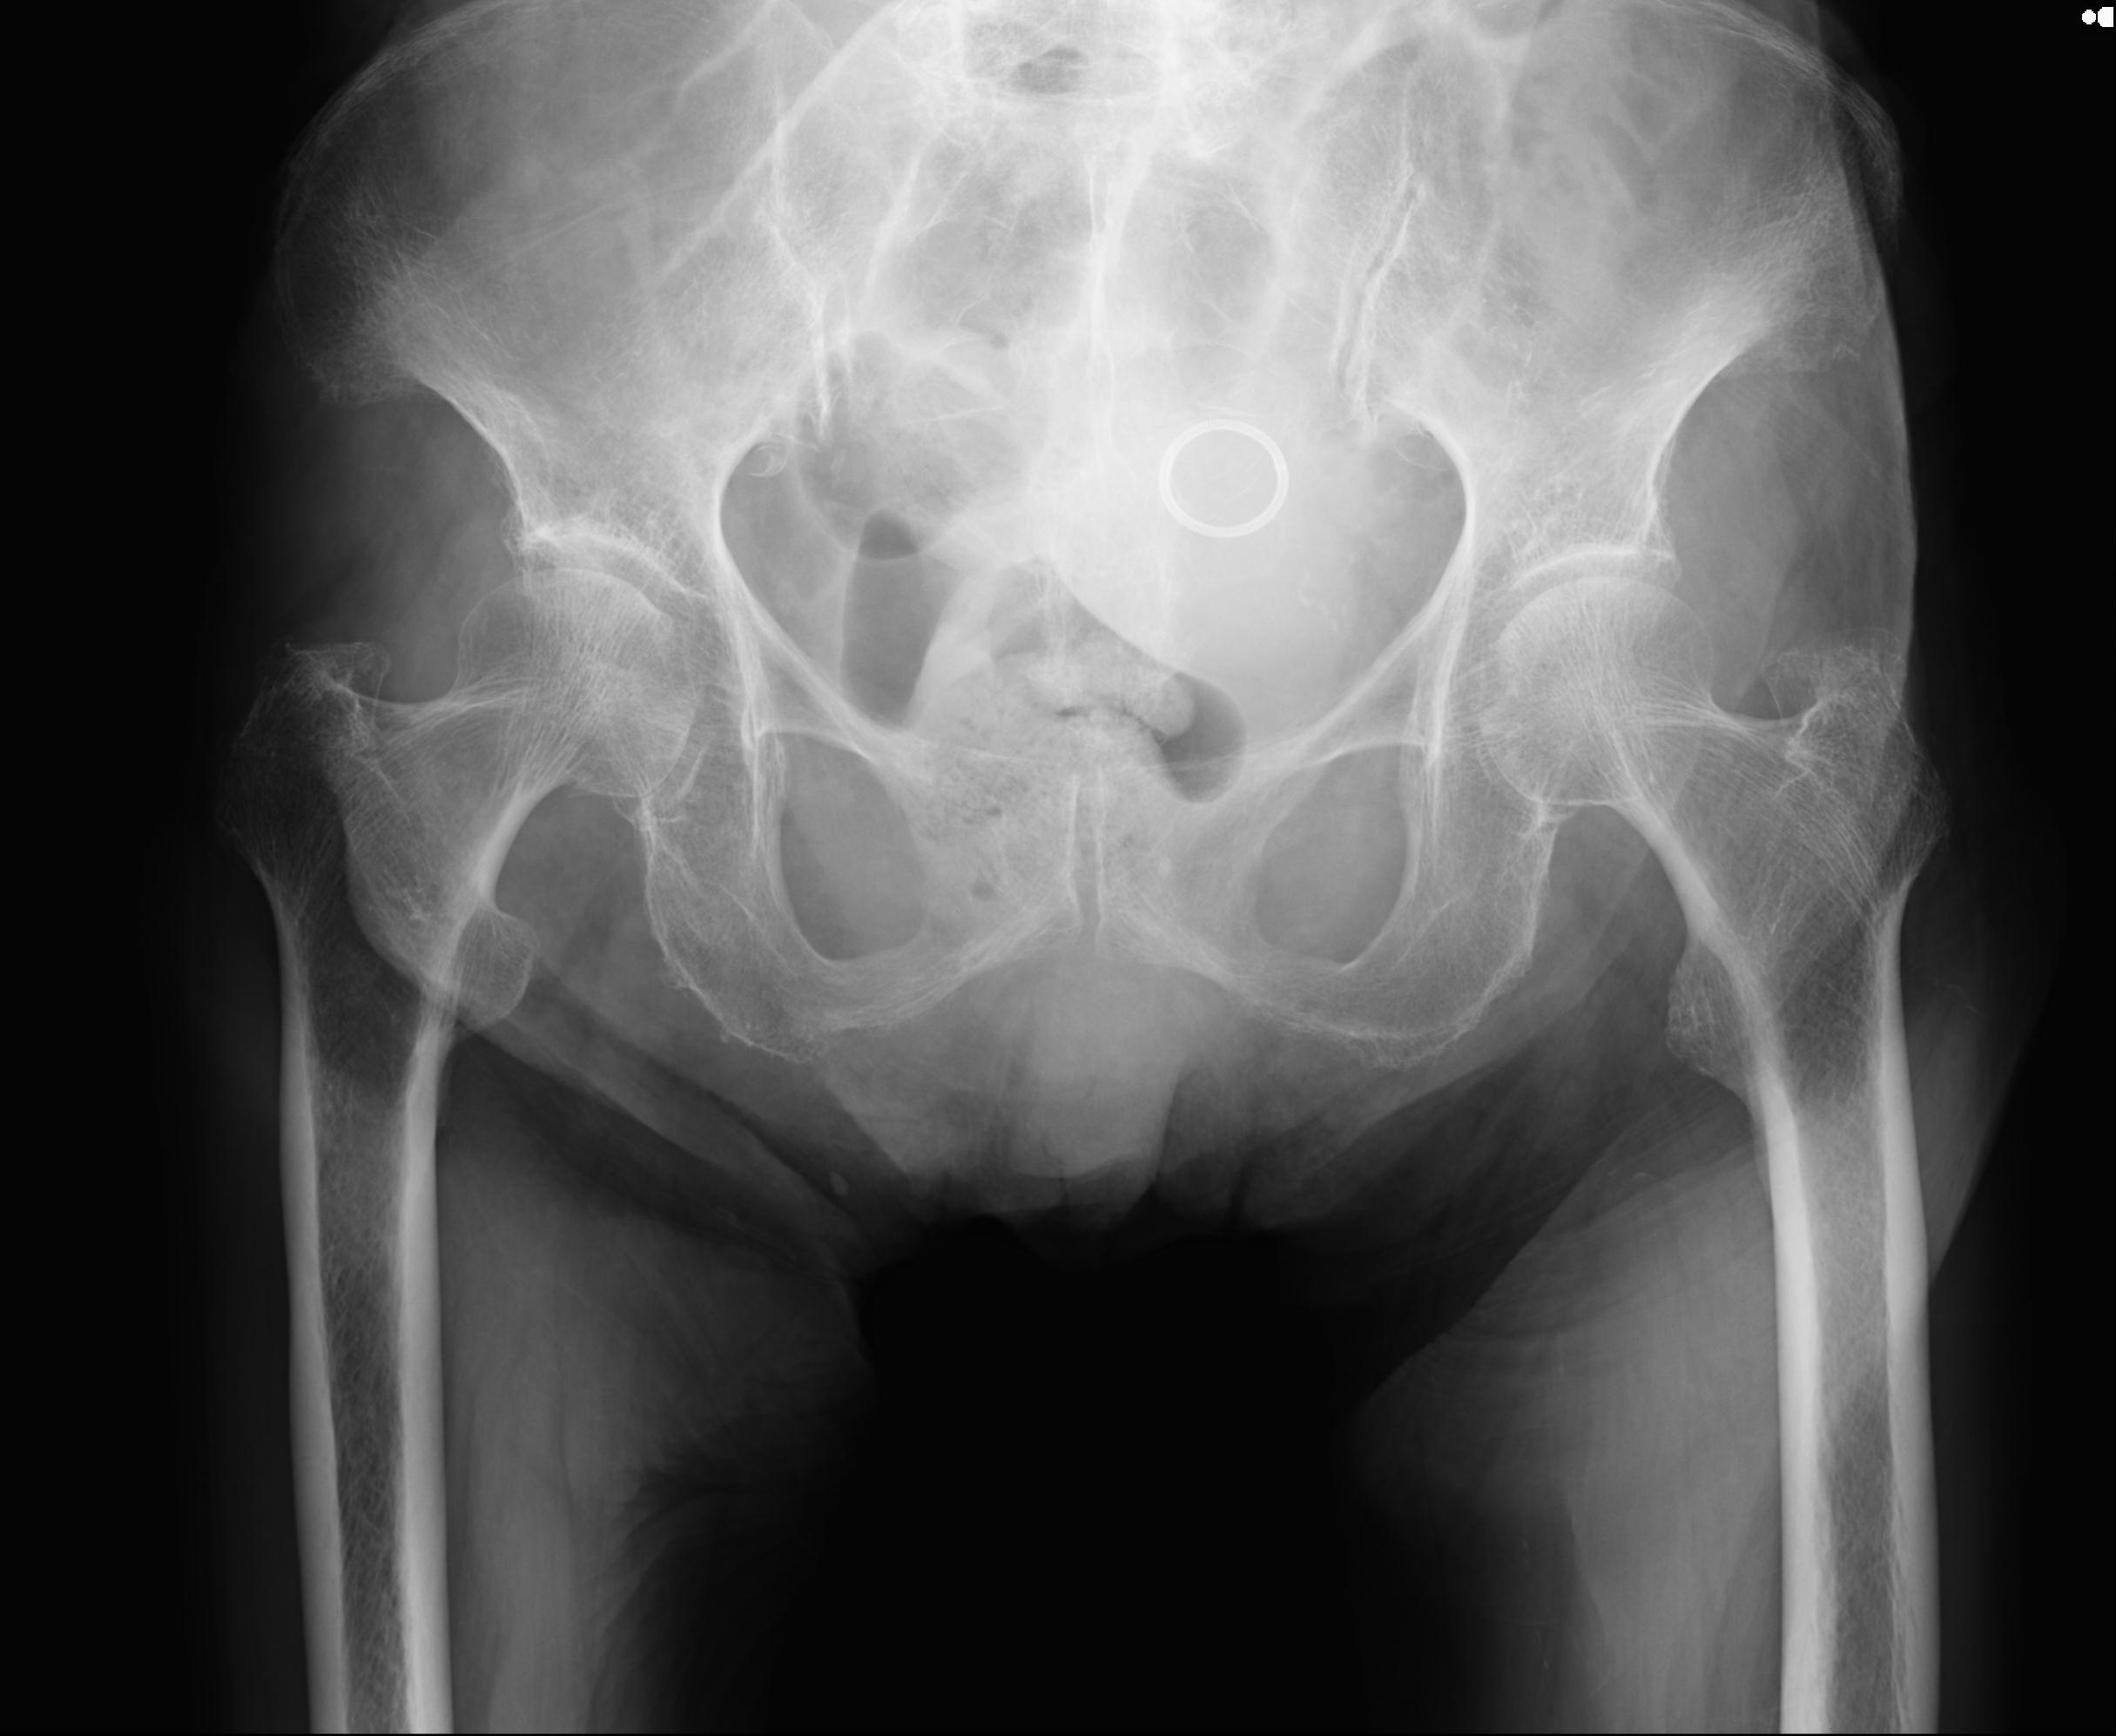

100703 1/27 両股正面+軸 1/29 両股正面+軸 94歳女性 パンソンロン

46666 1/28 両股正面+軸と 1/26 右手関節 2R 76歳女性 右転子部骨折

37 1/18 両股正面+軸 1/22 2R 86歳女性 右転子下

91569 3/25 両股正面とラウエン 70歳女性 人工骨頭+バンクーバー